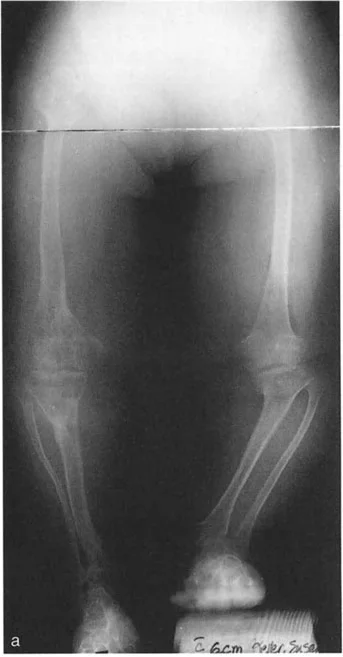

* الأشعة السينية (X-rays) الواقفة لكامل الطرف السفلي: هذه الأشعة ضرورية لتقييم المحاذاة الكلية للطرف السفلي تحت تأثير وزن الجسم. يطلب الأستاذ الدكتور محمد هطيف صورًا شعاعية كاملة الطول للساق أثناء الوقوف (Full-length standing alignment films) لتقييم المحور الميكانيكي للساق وتحديد زوايا المفاصل بدقة.

* نقص تنسج الشظية (Fibular Hemimelia): وهي حالة يولد فيها الطفل بشظية (عظم الساق الأصغر) أقصر من الطبيعي أو مفقودة جزئيًا. هذا يؤثر بشكل كبير على نمو قصبة الساق والكاحل، مما يؤدي إلى تشوهات شديدة في المحاذاة منذ الولادة. في هذه الحالات، يكون مركز دوران التشوه (CORA) عادةً عند مستوى المفصل نفسه.